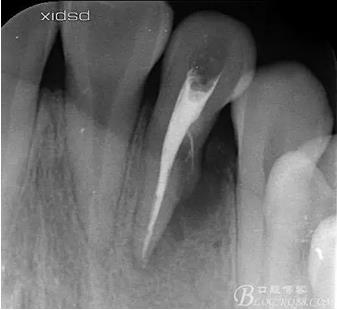

(1) 檢查:12唇側(cè)牙齦可見竇道,牙體顏色較鄰牙暗,無光澤,形態(tài)完整無缺損,唇側(cè)及近遠中向未提及牙周袋。腭側(cè)齦緣輕度紅腫,舌側(cè)窩可探及裂溝,可見浸墨狀痕跡,沿裂溝舌側(cè)探診牙周袋深大于11mm,除患牙外全口牙周狀況良好,為探及牙周袋,牙齦色粉紅。邊緣菲薄,質(zhì)地堅韌。12冷熱診無反應,叩診(+-),無明顯松動,無咬合創(chuàng)傷。12根尖x線片示,根管中三分之一中可見一斜向線樣透射影像根尖區(qū)及遠中根三分之一可見低密度透射暗影,錐形束CT示12根尖區(qū)唇腭向骨吸收已穿通,根面溝達根中三分之一卷曲分出另一牙根,再未見其他明顯的根管系統(tǒng)。